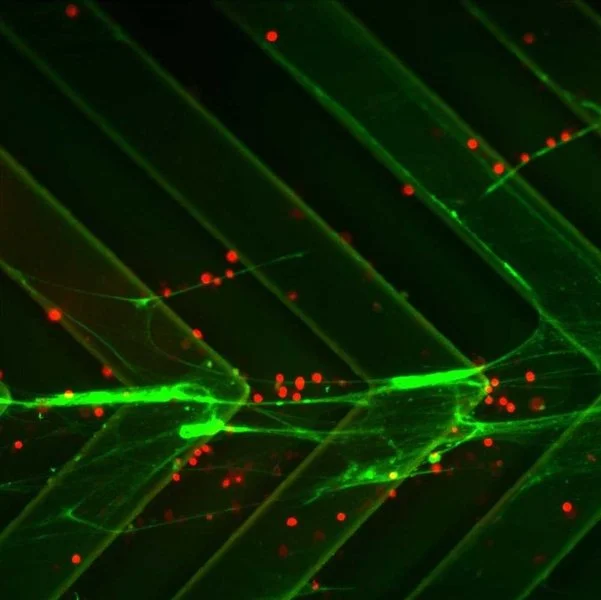

The research at the Bose Lab lies at the interface of biomaterial science, cellular engineering, and drug delivery with the aim of creating next-generation cell-based therapies for a wide range of human diseases. The lab combines multiscale device fabrication, material chemistry, and cell engineering principles to develop platform technologies capable of delivering precise doses of drugs (biologics) at the right location in the body at the right time. These platforms have applications in treating chronic diseases such as diabetes and liver failure, immune engineering applications in cancer and autoimmunity, and regenerative medicine.

“The Bose laboratory combines multiscale device fabrication, material chemistry, and molecular and cell engineering principles to gain insights into fundamentals of cellular interactions and apply these discoveries to design effective cell-based therapies”